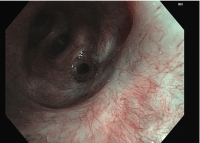

Bronchoskopie

Abbildung 4: Bronchoskopie